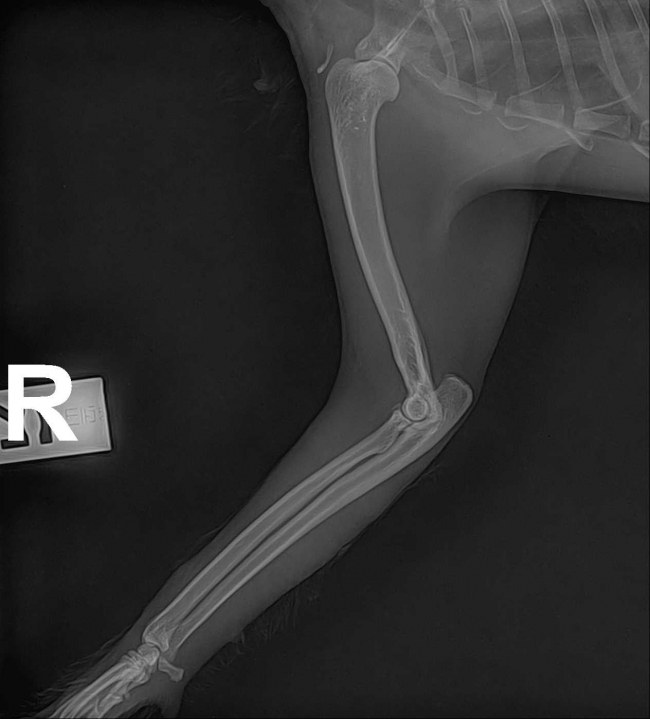

치료중 대상묘

치료완료후